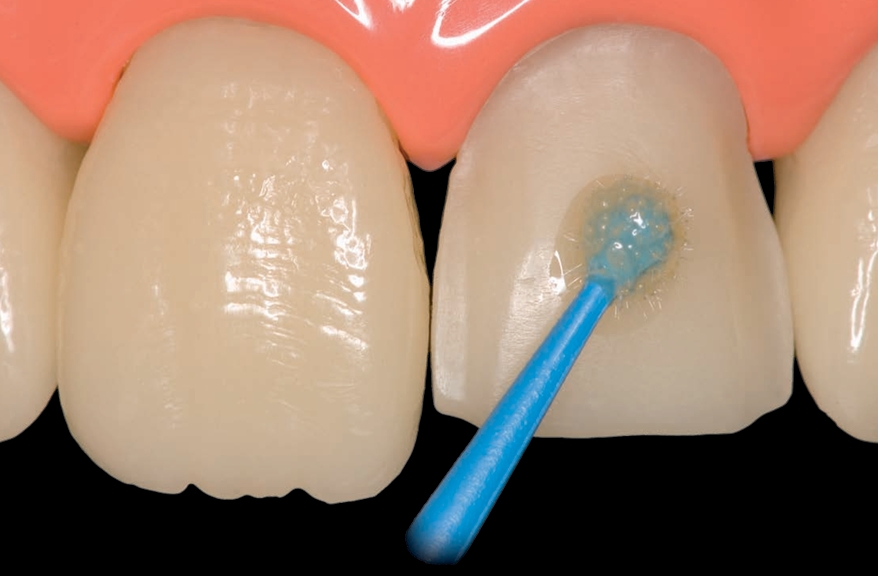

A hipersensibilidade dentinária pode ser mensurada com escalas e tratada em protocolo de sessão única. Veja mais.